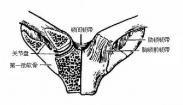

肘关节结核

628健康网为您分享有关肘关节结核的症状,肘关节结核的治疗方法,肘关节结核的预防知识,肘关节结核的症状图片,肘关节结核...